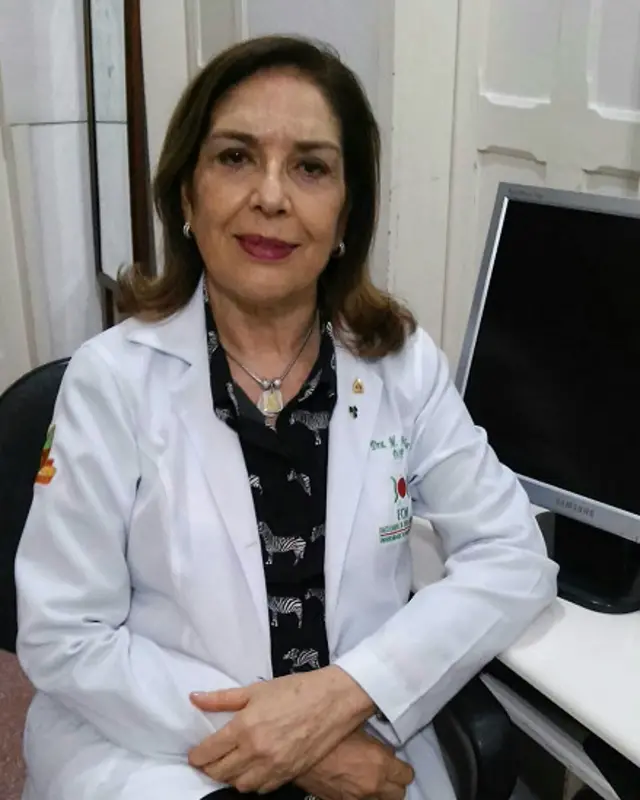

A infectologista pediátrica pernambucana Maria Angela Rocha, de 67 anos, acompanhou desde o início a epidemia de microcefalia que agora assusta o país. Ela é coordenadora do setor do Hospital Universitário Oswaldo Cruz (HUOC), em Recife, que tem concentrado a maior parte do atendimento aos bebês com a má-formação no Estado.

Confira o depoimento da médica à BBC Brasil:

"O serviço que coordeno é um serviço de referência em infecções congênitas. Para nós, tudo começou no finalzinho de agosto e começo de setembro. Nos últimos dias de agosto começaram a chegar três, quatro casos (de bebês com microcefalia) encaminhados por neurologistas. Antes, passávamos meses sem ver um caso. O Estado tinha uma média de nove casos por ano.

Ficávamos nos perguntando: 'o que será que está acontecendo?'. Mas quando, no final de setembro, começou a aumentar a procura, foi quase desesperador. Nos chocou, porque todo dia chegavam casos. Tomamos consciência de que a coisa tinha uma proporção que não estávamos esperando. No dia 27 de outubro, fizemos a notificação ao Estado e ao Ministério da Saúde.

Nosso ambulatório já estava lotado e agora está superlotado, porque em princípio temos que acolher todas as crianças. E como somos um serviço de referência, há muitas.

O Estado está descentralizando o atendimento também para três cidades no interior, mais distantes, que poderão seguir o protocolo que estamos seguindo e fazer os mesmos exames. Apesar das suspeitas (de associação com o zika vírus), temos que fazer uma investigação bem isenta.

Esses casos normalmente vêm para nós para sabermos qual o agente causador e acabam sendo acompanhados pelos neurologistas. Dos 487 casos notificados em Pernambuco, estamos avaliando cerca de 100 no momento. Nossa equipe toda está envolvida.

A primeira coisa que fazemos é conferir a cabeça da criança e conversar com a mãe, detalhar como foi o parto, se ela usou drogas lícitas ou ilícitas, medicamentos, se fumou, se teve alguma doença, etc. Em paralelo, pedimos a tomografia e os exames de sangue da criança. A partir daí avaliamos os resultados.

Assumi o serviço de infectologia (do HUOC) há mais de 20 anos. Já vi a pólio lá atrás, o cólera, o (vírus da gripe) H1N1, surtos de difteria e de sarampo. Mas não vi nada desse jeito e com essas consequências, é bem inusitado.

Segundo a infectologista Maria Angela Rocha, a microcefalia é uma má-formação não muito frequente, que pode ocorrer por alterações genéticas ou ser causada por infecções contraídas pela gestante entre o primeiro e o quarto mês de gravidez.